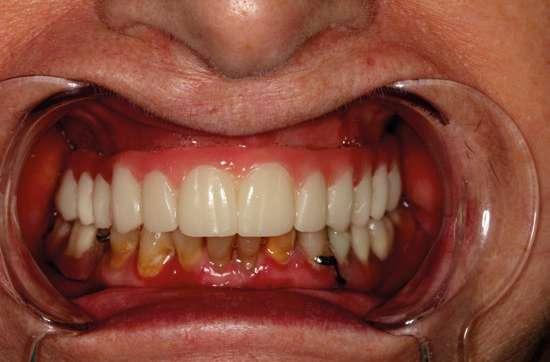

Se monitorizó la evolución de la cicatrización durante las semanas siguientes y se fue adaptando la prótesis provisional a los cambios gingivales mediante silicona de rebase blando. (Ufi Gel SC Voco). Pasados cuatro meses, procedimos a realizar la exposición de los implantes y la conexión de los pilares Multi-unit Xeal™ rotatorios mediante un protocolo One abutment- One time. Durante la segunda cirugía, nos aseguramos de dejar un tejido blando de suficiente grosor y altura de encía queratinizada que nos garantice un mantenimiento del hueso crestal. Se seleccionaron las alturas y angulaciones de estos y se colocaron a 35 Nw de torque. La topografía y las propiedades químicas de estos pilares han sido diseñadas para facilitar la adhesión del tejido blando al pilar y así tener una mejor barrera que proteja el hueso subyacente. Al colocar estos pilares logramos igualar las alturas de las plataformas de los implantes, siendo más cómoda la realización de la prótesis definitiva y también mejorando la higienización de la futura prótesis. (Fig. 12 y 13).

Para poder evaluar la oclusión, estética, dimensión vertical, sellado gingival, etc., usamos pruebas plásticas impresas en 3D diseñadas en Exocad. Sobre éstas hacemos todos los retoques necesarios y una vez controlados, se retornan o se re-escanean para que el laboratorio copie la prueba en resina en la prótesis final. Esto nos permite eliminar el ajuste final en boca del paciente, evitando tener que hacer retoques que provoquen la pérdida de anatomía, así como la generación de superficies abrasivas en las prótesis una vez fabricadas y también evitamos los procedimientos de repulido, que a menudo resultan insatisfactorios. (Fig 17 y 18).